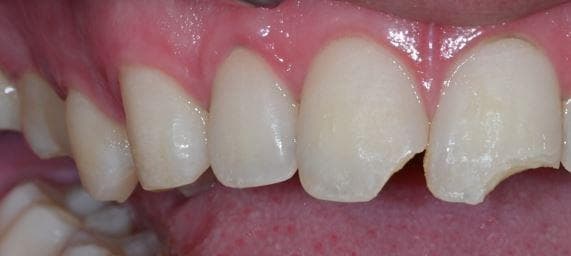

이빨이 부셔졌는데 해당 내용 관련하여 치료방법 문의드립니다.

사진상의 왼쪽,오른쪽 둘다 크라운을 하기로했습니다

왼쪽은 레진으로 치료받아도 상관없을까요

파절부위가 저정도면 레진으로 치료가 가능한지 여쭤봅니다

추후 1.크라운 2.레진 둘다 충치에 대해서 어떤게 관리하기 편할까요..?

1. 충치의 경우 크라운은 크라운 자체를 해체해야 확인이 가능하고 레진은 수시로 확인이 가능해서 여쭤봅니다

2. 레진으로 치료한다쳐도 탈락위험이 클까요?

레진으로 치료가 가능한 정도로 보이며 파절될 가능성은 아무래도 높습니다만 크라운을 하기는 조금 아까운 듯 합니다.

저부위에 레진으로 하게되면 잘 떨어질 가능성이 높습니다. 크라운으로 하시는게 좋을것같습니다.

사진으로 봤을 경우에는 손실된 치아의 양이 많아 보입니다. 레진으로 충전을 할 수도 있지만 충전을 했을 경우 탈락이 쉬울 수 있습니다.